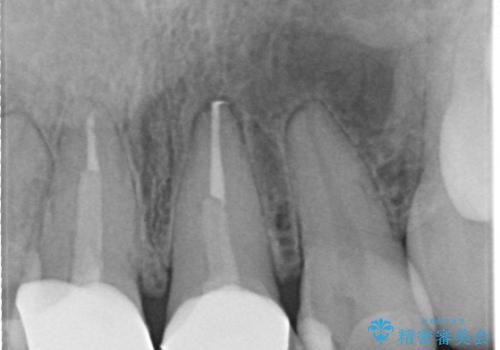

- [前歯の色が気になる」を主訴に来院された患者様です。歯の形を整えた後オールセラミッククラウンで治療を行いました。

以前他院にてセラミッククラウンを被せていたのですが、セメントの劣化なのか色が青白くなっていました。

歯の形を整えた後、色が透けないよう処置をしてオールセラミッククラウンで治療を行いました。